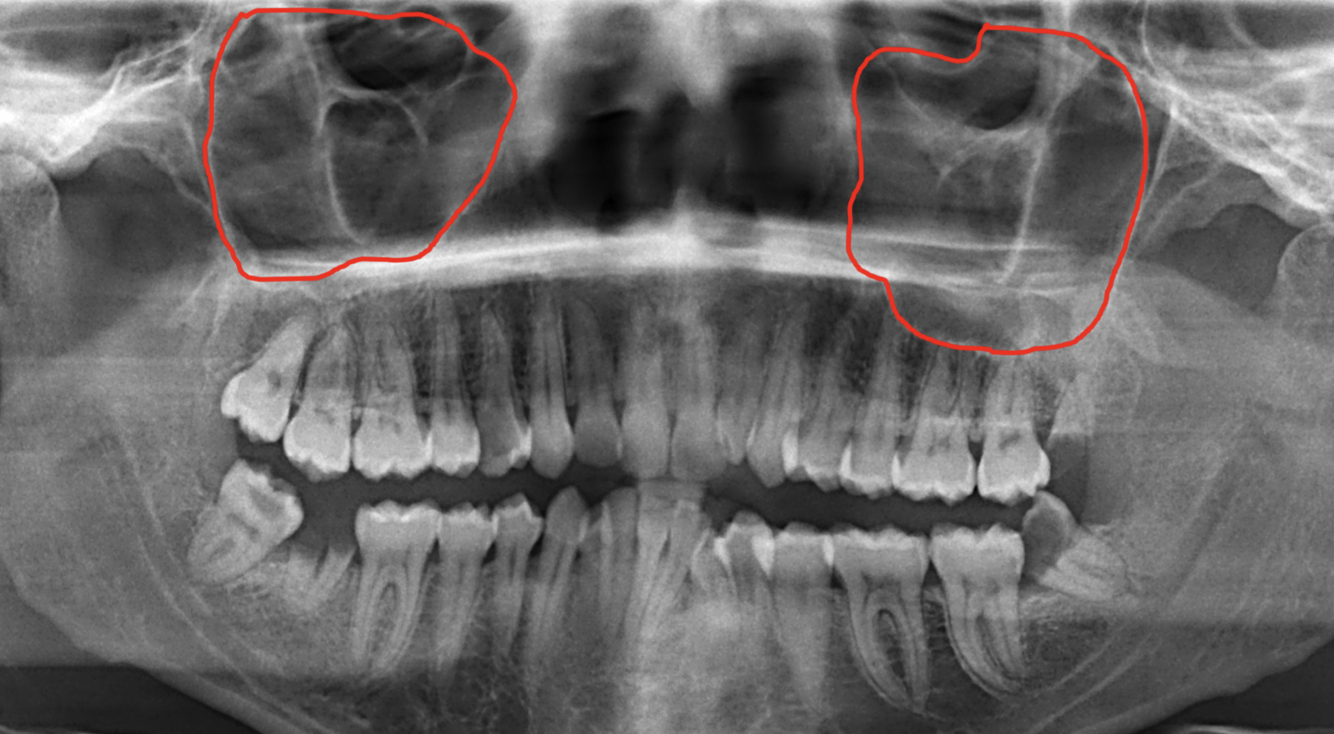

What does the red indicate in the following image?

A

Maxillary sinus